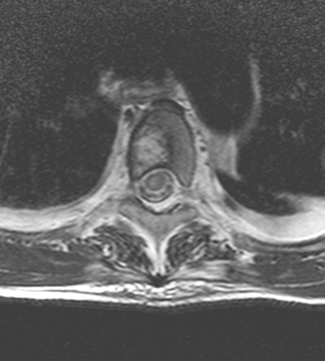

Syrinx describes the condition when cerebrospinal fluid enters the interior of the spinal cord and forms a cavity in its center in a tube or a flute- like manner. It can even be a few segments long.

MRI: only MRI can provide a definitive diagnosis by depicting the expanded region within the axis of the spinal chord as an expansile lesion showing liquor intensity on all sequences (weak T1 signal and strong on T2 weighted imaging).